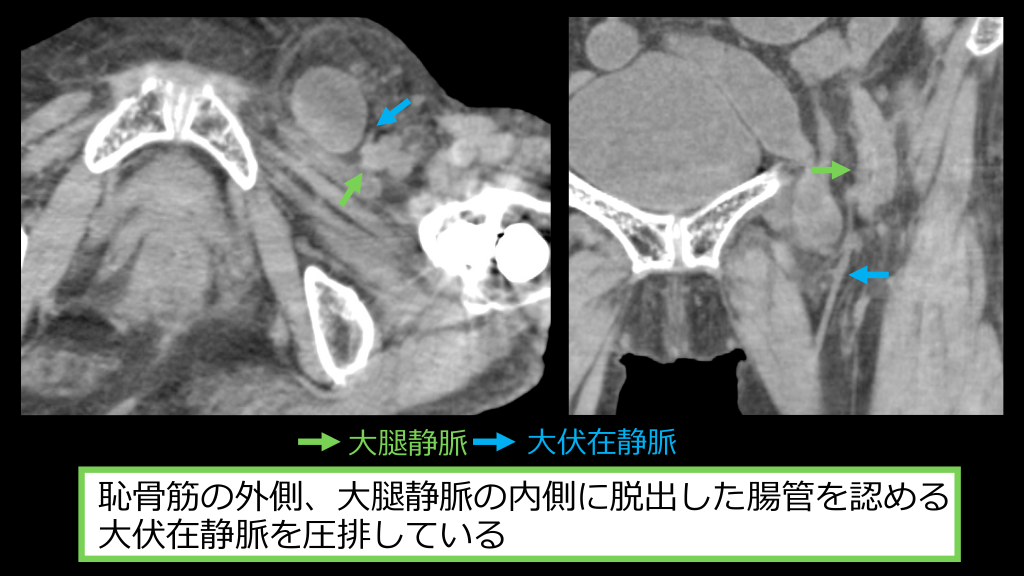

02 症例3 診断︓⼤腿ヘルニア嵌頓 腹部臓器が⼤腿管を通り、伏在裂孔へ脱出する外ヘルニア。 出産や加齢による筋膜の脆弱化が主要因と⾔われ、⾼齢⼥性に多い。 ヘルニア⾨が狭⼩のため嵌頓しやすい。 ⿏径ヘルニアとの画像所⾒の違い ・⿏径靱帯の背側に脱出する ・⼤腿静脈、⼤伏在静脈に沿って脱出する ・⼤伏在静脈を圧排し変形させる ①内⿏径ヘルニア②外⿏径ヘルニア③⼤腿ヘルニア 画像診断別冊KEY BOOKシリーズわかる︕役⽴つ︕消化管の画像診断/ESPRESSO腹部画像診断

⼤腿静脈 ⼤伏在静脈 恥⾻筋の外側、⼤腿静脈の内側に脱出した腸管を認める ⼤伏在静脈を圧排している